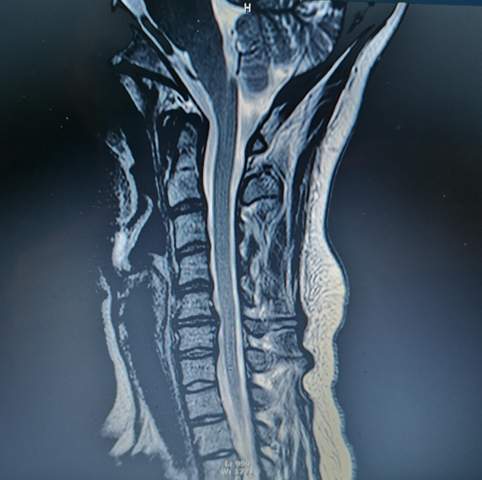

Verletzungen des Auges selbst oder seiner zugehörigen Strukturen. Neben muskulären Verspannungen kann auch ein Gelenkverschleiß Ursache der Beschwerden sein. Sehnerventzündung Tumore ein erhöhter Augeninnendruck sowie Durchblutungsstörungen unterschiedlichster Ursache können auf den Sehnerv drücken und diesen dauerhaft schädigen.

Oftmals ist die Lichtscheu auf eine Entzündung der Hornhaut Keratitis zurückzuführen. Eine mögliche Ursache von Sehstörungen im Rahmen eines HWS-Syndroms sind daher Durchblutungsstörungen der Augen.